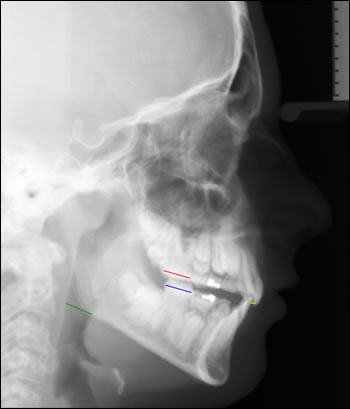

Fig 2: This cephlometric image was taken upon completion of Twin Block therapy. Notice the overjet (yellow line) is reduced. The lower molar (blue line) is now in front of the upper molar (red line). The airway (green line) has also improved. The jaws are now in an ideal Skeletal Class I relationship. Also, notice how the soft tissue, or facial profile has improved.